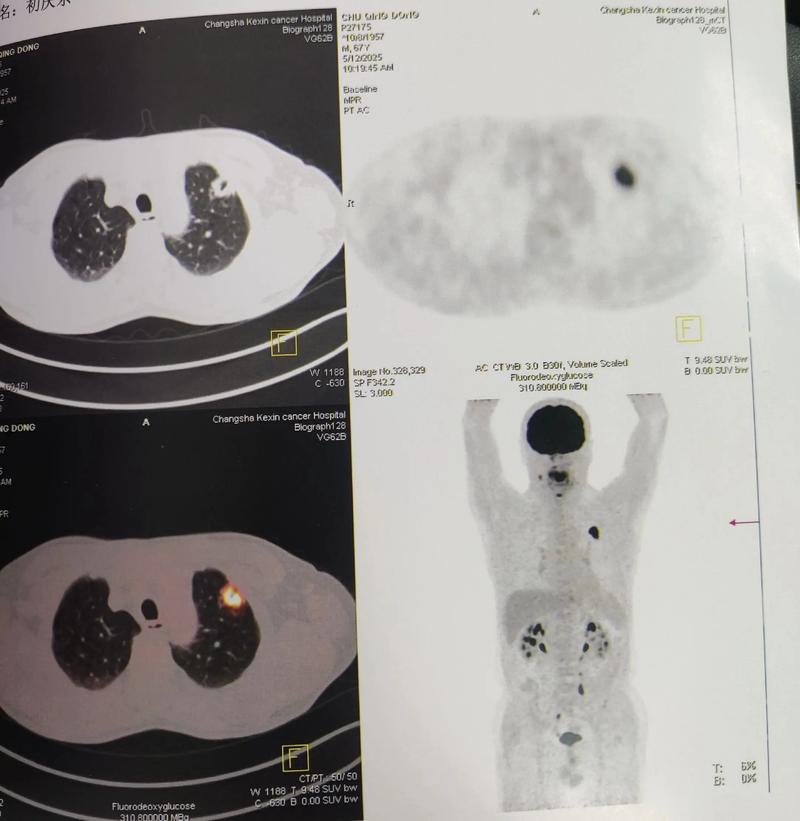

这是PET-CT在神经领域一个极其重要的应用,约30%的脑梗塞患者常规检查找不到明确原因,这些被称为“隐源性卒中”,PET-CT可以帮助寻找“隐藏的”病因。

- 血管炎: 使用18F-FDG PET可以清晰地显示受累血管壁的异常高代谢(炎性反应),这对于诊断和评估大血管炎(如巨细胞动脉炎)引起的脑梗塞非常有帮助。

- 心脏来源的栓塞: 对于怀疑心源性栓塞(如房颤)但常规检查难以证实的患者,18F-FDG PET可以发现心脏瓣膜、心房或大血管的感染性心内膜炎或恶性肿瘤(如粘液瘤),这些是潜在的栓子来源。

c) 评估肿瘤或炎症

- 肿瘤: 肿瘤细胞通常葡萄糖代谢异常旺盛,在18F-FDG PET上表现为明显的高代谢灶,这与梗塞灶的低代谢形成鲜明对比。

- 炎症/感染: 炎症病灶或感染灶(如脑脓肿)也会表现为FDG高摄取,有助于鉴别诊断。